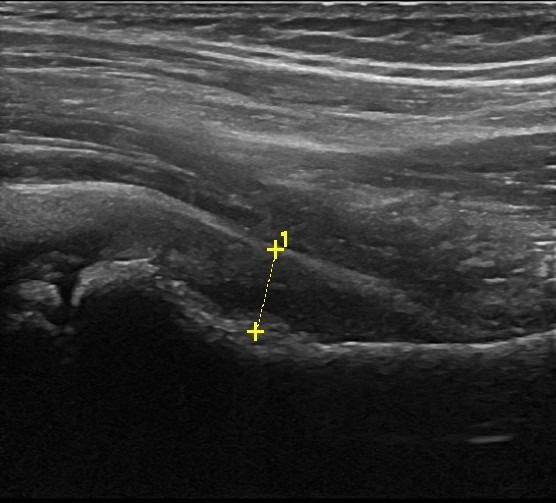

- Τενοντοπάθεια ή ρήξη γλουτιαίων τενόντων, ορθού μηριαίου και οπίσθιου μηριαίου

- Τροχαντηρίτιδα: συλλογή υγρού στους θυλάκους των γλουτιαίων τενόντων στο μείζονα τροχαντήρα

Η διαδικασία του Υπερηχογραφήματος του Ισχίου είναι απλή, ανώδυνη και δεν απαιτεί προετοιμασία από τον ασθενή. Κατά τη διάρκεια της εξέτασης, ο ασθενής ξαπλώνει στο εξεταστικό κρεβάτι, η Ιατρός εφαρμόζει ζελέ στο δέρμα της περιοχής και πραγματοποιεί την εξέταση με ηχοβολέα κατάλληλης συχνότητας. Υπό την καθοδήγηση της Ιατρού, ο ασθενής εκτελεί διάφορες κινήσεις με το πόδι του ως μέρος των δυναμικών δοκιμασιών. Η συνολική διάρκεια της εξέτασης είναι περίπου 30 λεπτά.